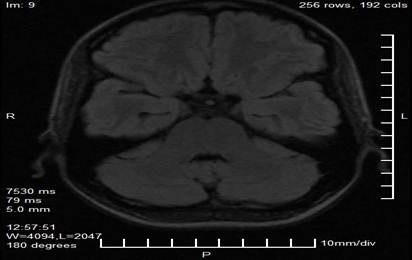

Complementary studies included a brain MRI with a neuro-ophthalmological protocol, which revealed a nodular, lobulated, well-defined image in the projection of the pineal gland, measuring 29 mm × 28 mm × 27 mm. The lesion had heterogeneous signal characteristics, with areas of hyperintensity on T1 and T2 sequences suggestive of a hemorrhagic or vascular component, and showed a compressive effect on the midbrain tectum and superior colliculi. No signs of obstructive hydrocephalus or intracranial hypertension were observed in the obtained slices (Figures 2 and 3).

Figure 3. Axial magnetic resonance imaging cut showing the extension of the pineal lesion and its anatomical relationship with the midbrain tectum and superior colliculi (shaded area).